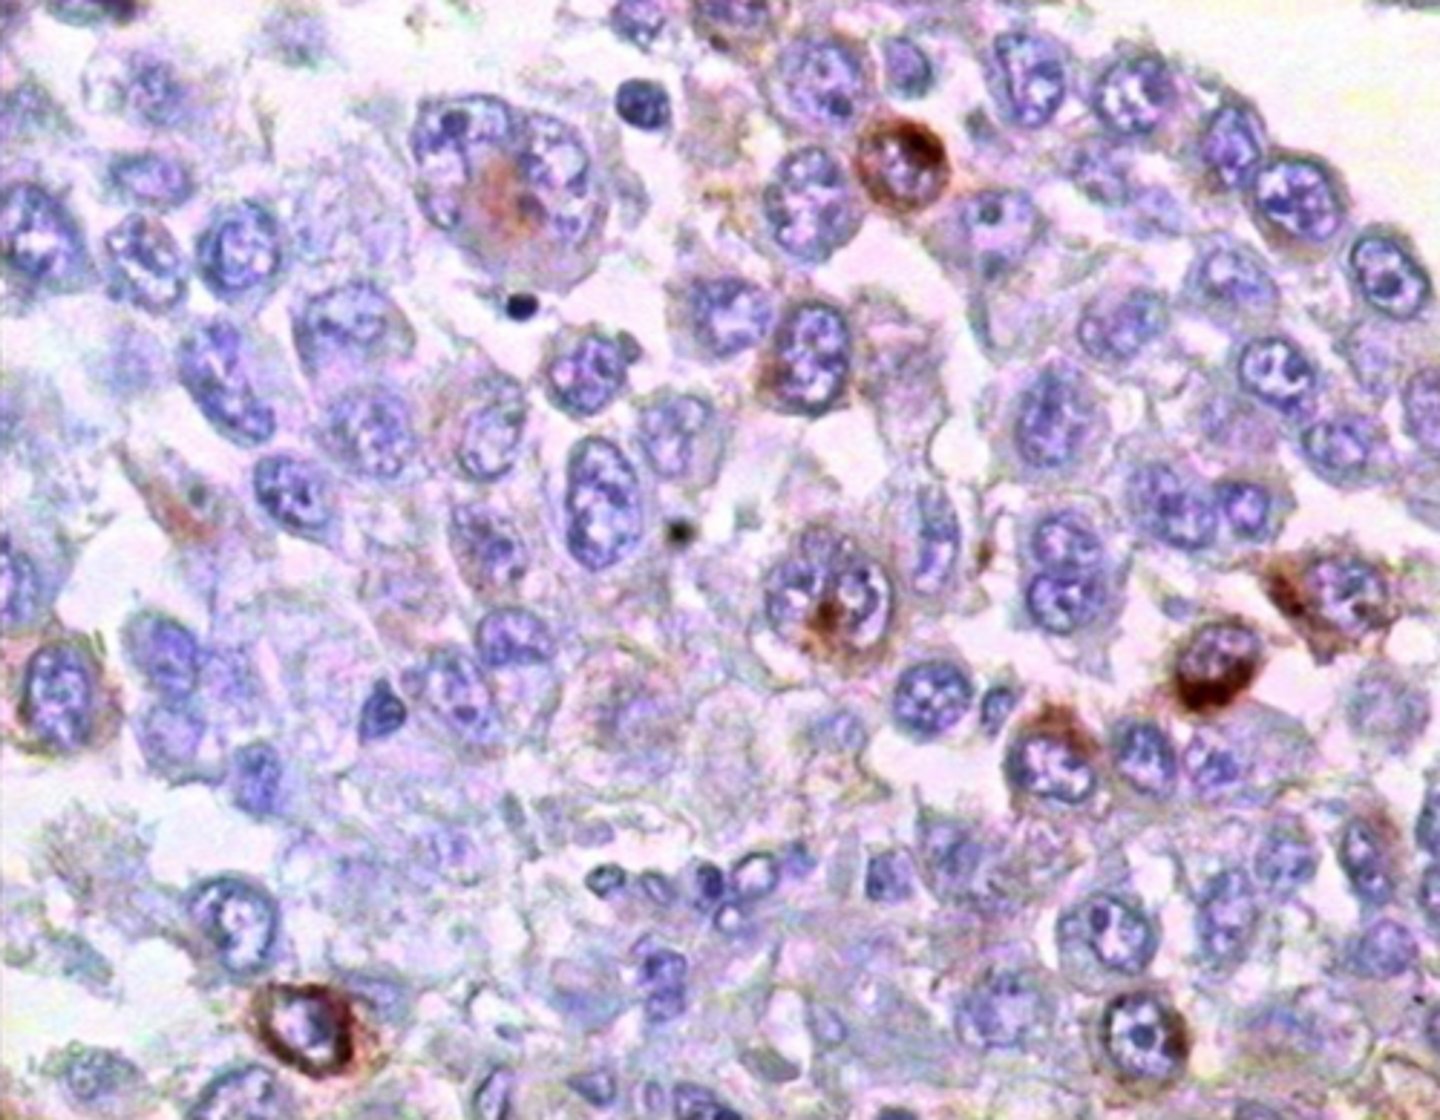

Melanoma: izteikta šūnu atipija un melanīna sintēze

Melanoma: INCI (intranukleāri citoplazmatiski ieslēgumi)